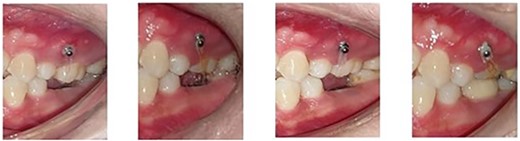

Allowed for placement of full coverage crown on the implant placed to replace the mandibular first molar (Fig. 4).

Full coverage crown placed on the implant to replace the mandibular first molar.